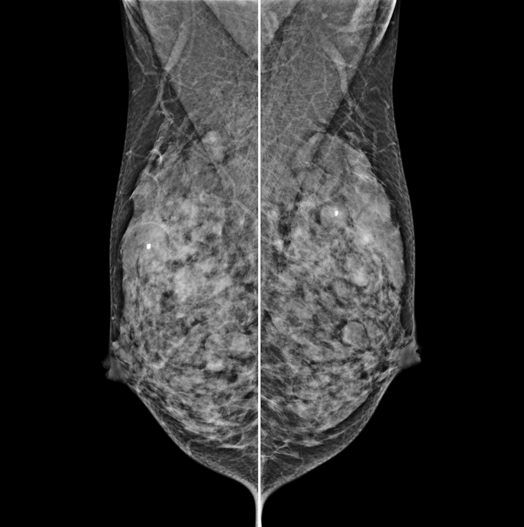

The X-ray tube moves on the breast and takes high-definition, high-resolution images with high contrast from various angles.

The images are reconstructed in 3D to provide accurate information about the location and condition of the lesion.

HESTIA supports "Synthetic 2D" that generates 2D images only by tomography shooting without additional 2D shooting.

GENORAY's know-how that was accumulated for a long time gives the best diagnostic images.